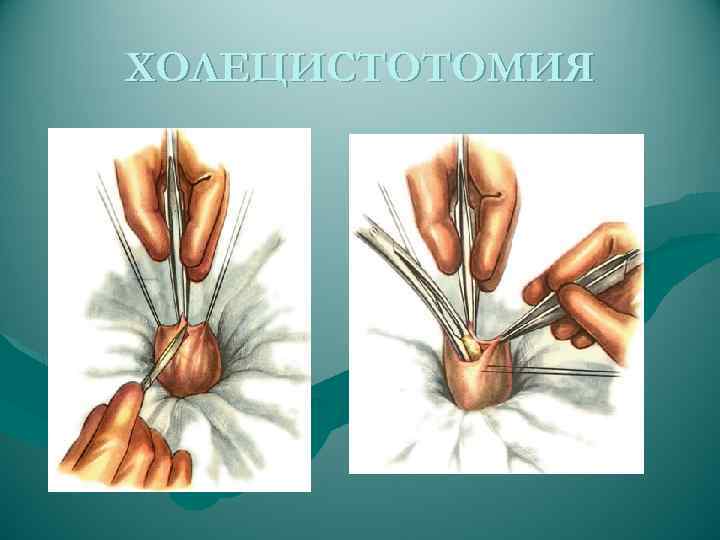

ХОЛЕЦИСТОТОМИЯ

ХОЛЕЦИСТОТОМИЯ